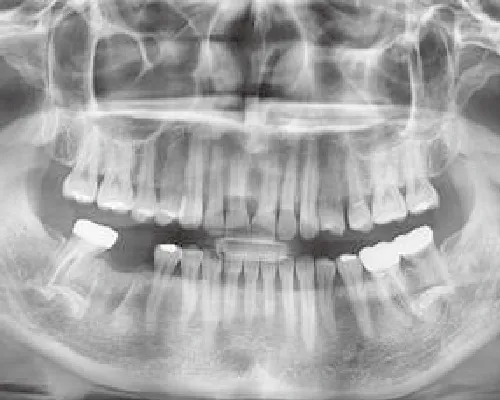

- ①各種検査

レントゲン検査(パノラマ、デンタル、CT、セファロ)

むし歯や歯周病の診査、咬み合わせの診査を行い、まずは骨の状態や歯肉の状態を正確に診断します。

| 診断 | ![]() 3D CT診断 |

![]() 2D x-ray診断 |